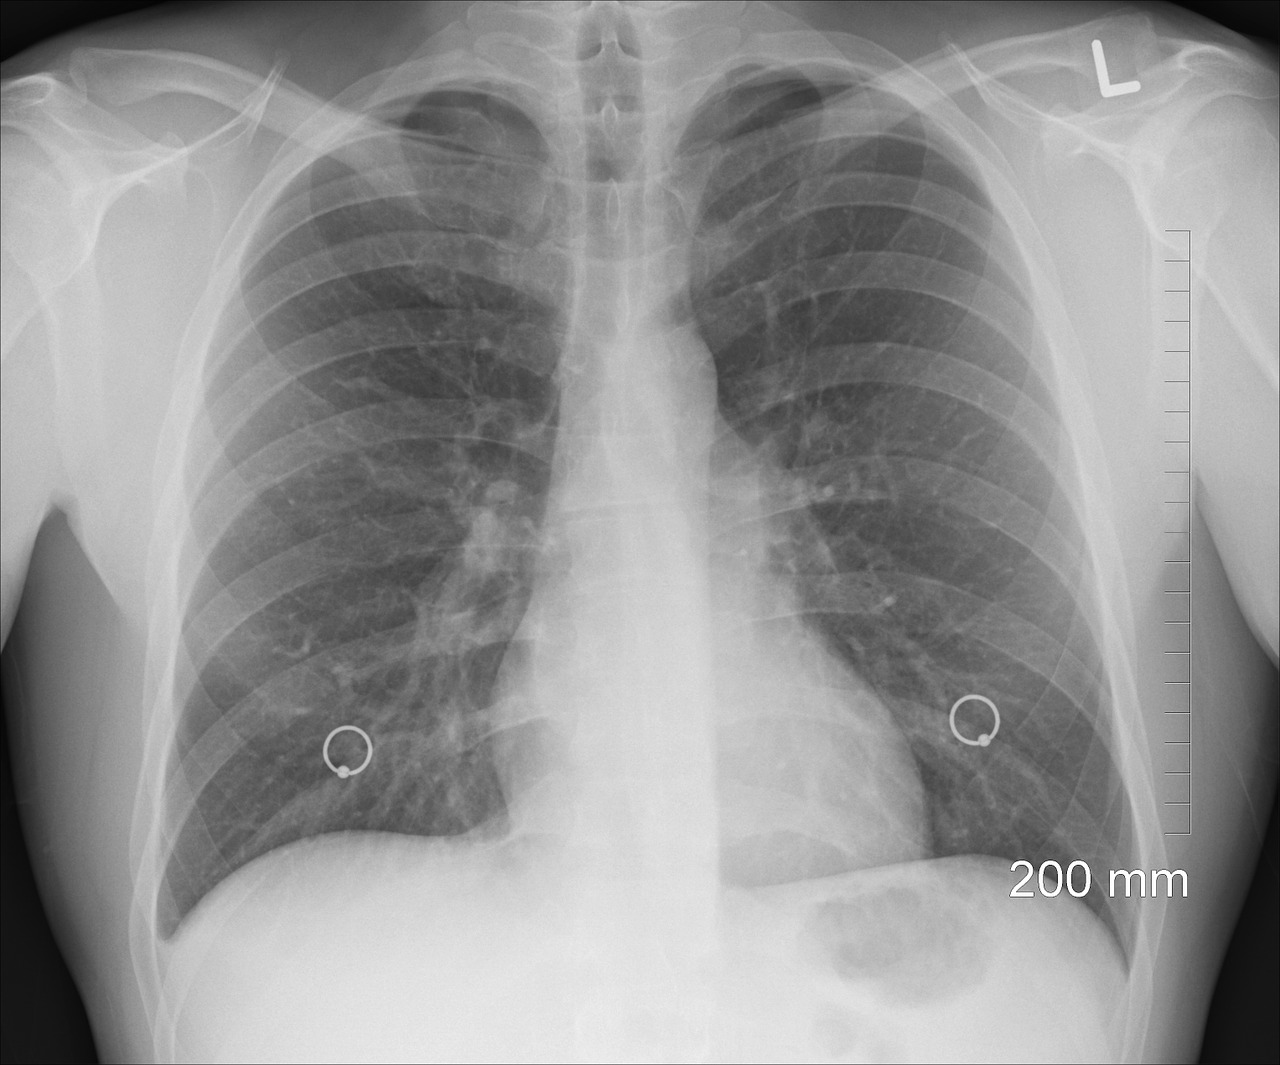

Os cientistas usaram um novo método para detectar lesões pulmonares que não são identificadas em exames de rotina.

A pneumologista Emily Fraser, autora principal do estudo, diz que é frustrante ver pessoas procurando ajuda médica sem conseguir explicar muito bem porque estão sem fôlego. Para piorar, na maioria das vezes, radiografias e tomografias computadorizadas não detectam essas anormalidades pulmonares.